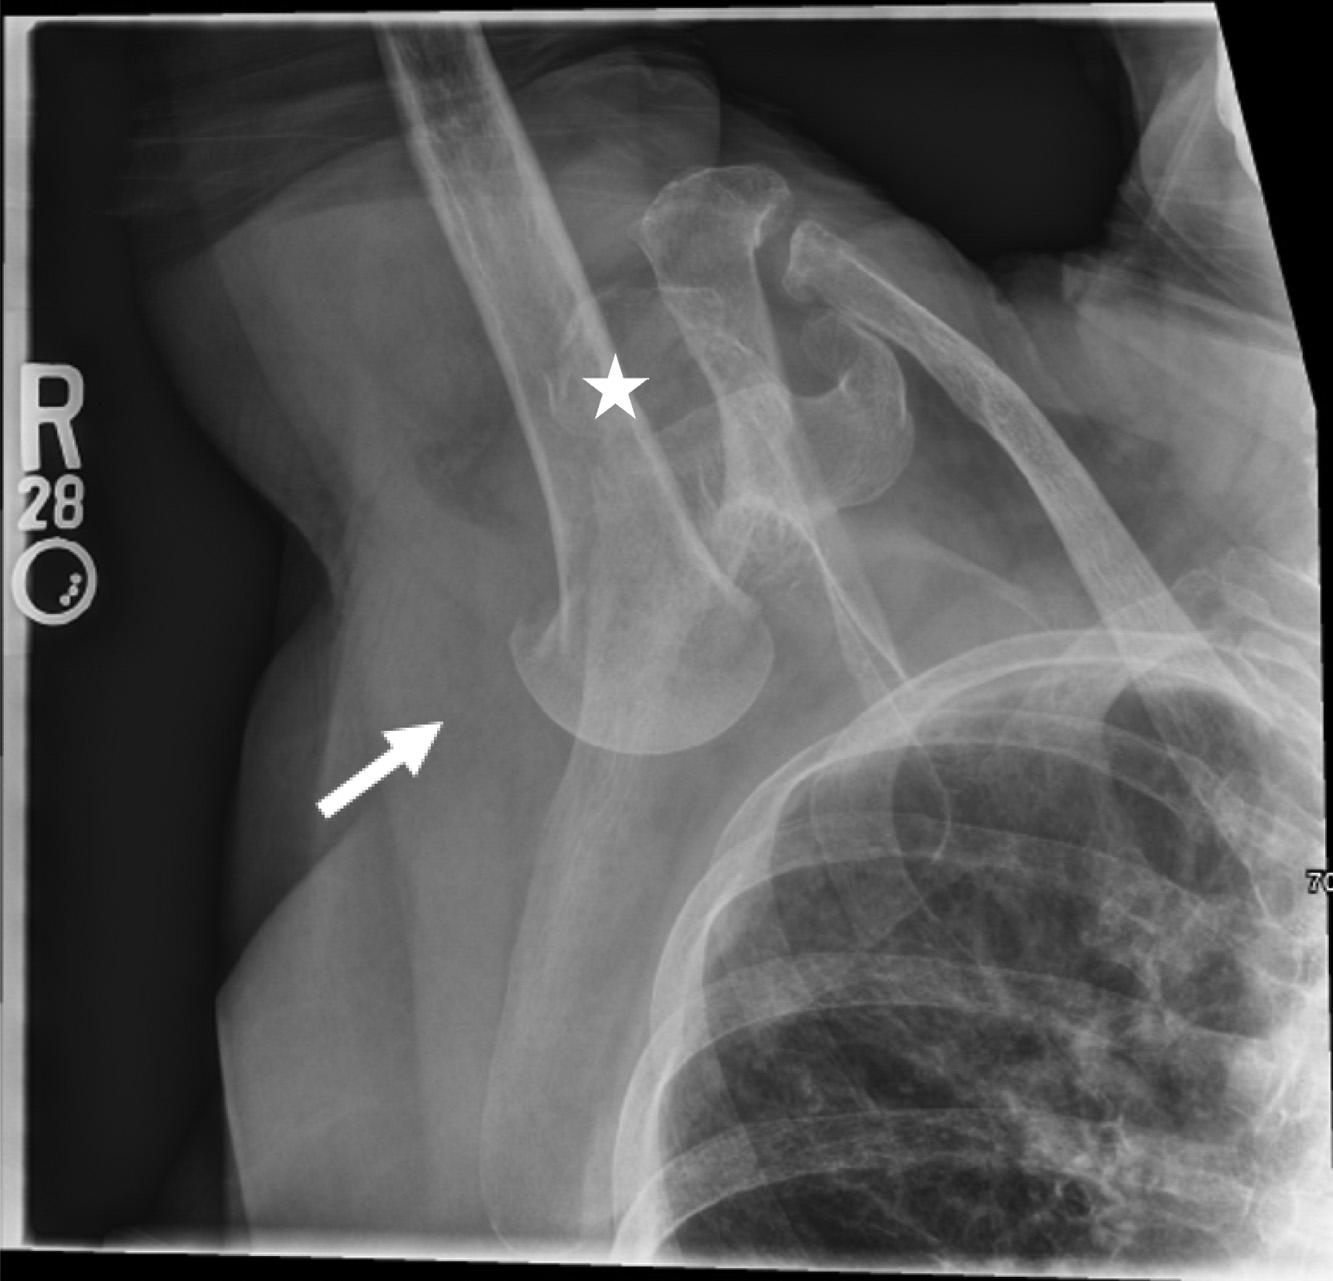

Initiallaboratoryresultsareshownin Table.An electrocardiogram(ECG)wasperformedandshowedasinus rhythmwithoutectopyorST-segmentchangesandwas unchangedfromhisprevioushospitalization.Chest radiography(CXR)wasobtained,shownin Image1.The radiologist’sinterpretationwas “[p]atchyopacityintheright lowerlobesuggestiveofpneumoniainthecorrectclinical setting.Goiterredemonstratedwhencomparedtoprevious. Normalcardiac findings.” Apoint-of-careultrasound (POCUS)oftheheartshowednopericardialeffusion,no suggestionofrightventriclestrain,novolumeoverload,and anormalleftventricle.

Image1. Initialchestradiographshowinganopacityintheright midlung(blackarrow)ina77-year-oldmanbeforeheexperienced arapidchangeinmentalstatus.

Lookingoverthelabsandimaging,Idonotbelievethey provideasignificantamountofnewinformationbutcouldbe usedtoremovesomedifferentials.Thepatient’schemistry hadsomeslightabnormalitiesbutnothingunexpectedgiven hiscomorbidities.Hiscoagulationstudieswereconsistent withsomeonewithcirrhosis.Thereweresomeabnormalities inhisthyroidfunctionpanel,butIdonotthinktheyexplain hisacutechange.Wealsodonotknowthetimingofhis levothyroxinedose,andhisthyroidstimulatinghormone indicatesthathehaslikelybeentakingit.Theetiologyof hematuriaisunclear,buthisurineisotherwisewithoutany signofinfection.Hiscompletebloodcountdoesshow leukocytosisaswellasmildanemia.Lastly,hisCXRis subtle,butanopacityintherightmidlung,asinterpretedby radiology,wouldbeconsistentwithhisabnormal breathsounds.